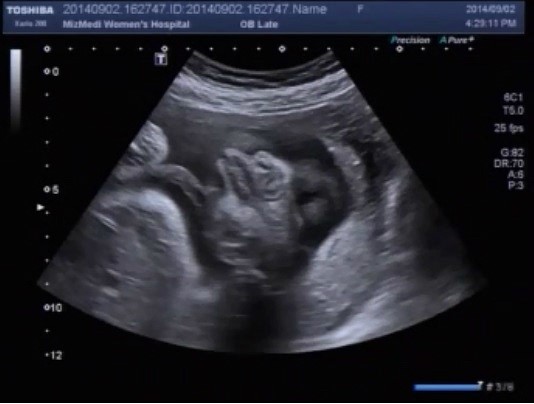

[태아초음파 동영상6] 미즈메디 정기검진 태아초음파 동영상

30주 3일 미즈메디 정기 검진 갔다 왔어요. 26주 6일때 입체 초음파를 찍고, 거진 한달만에 병원에 ...